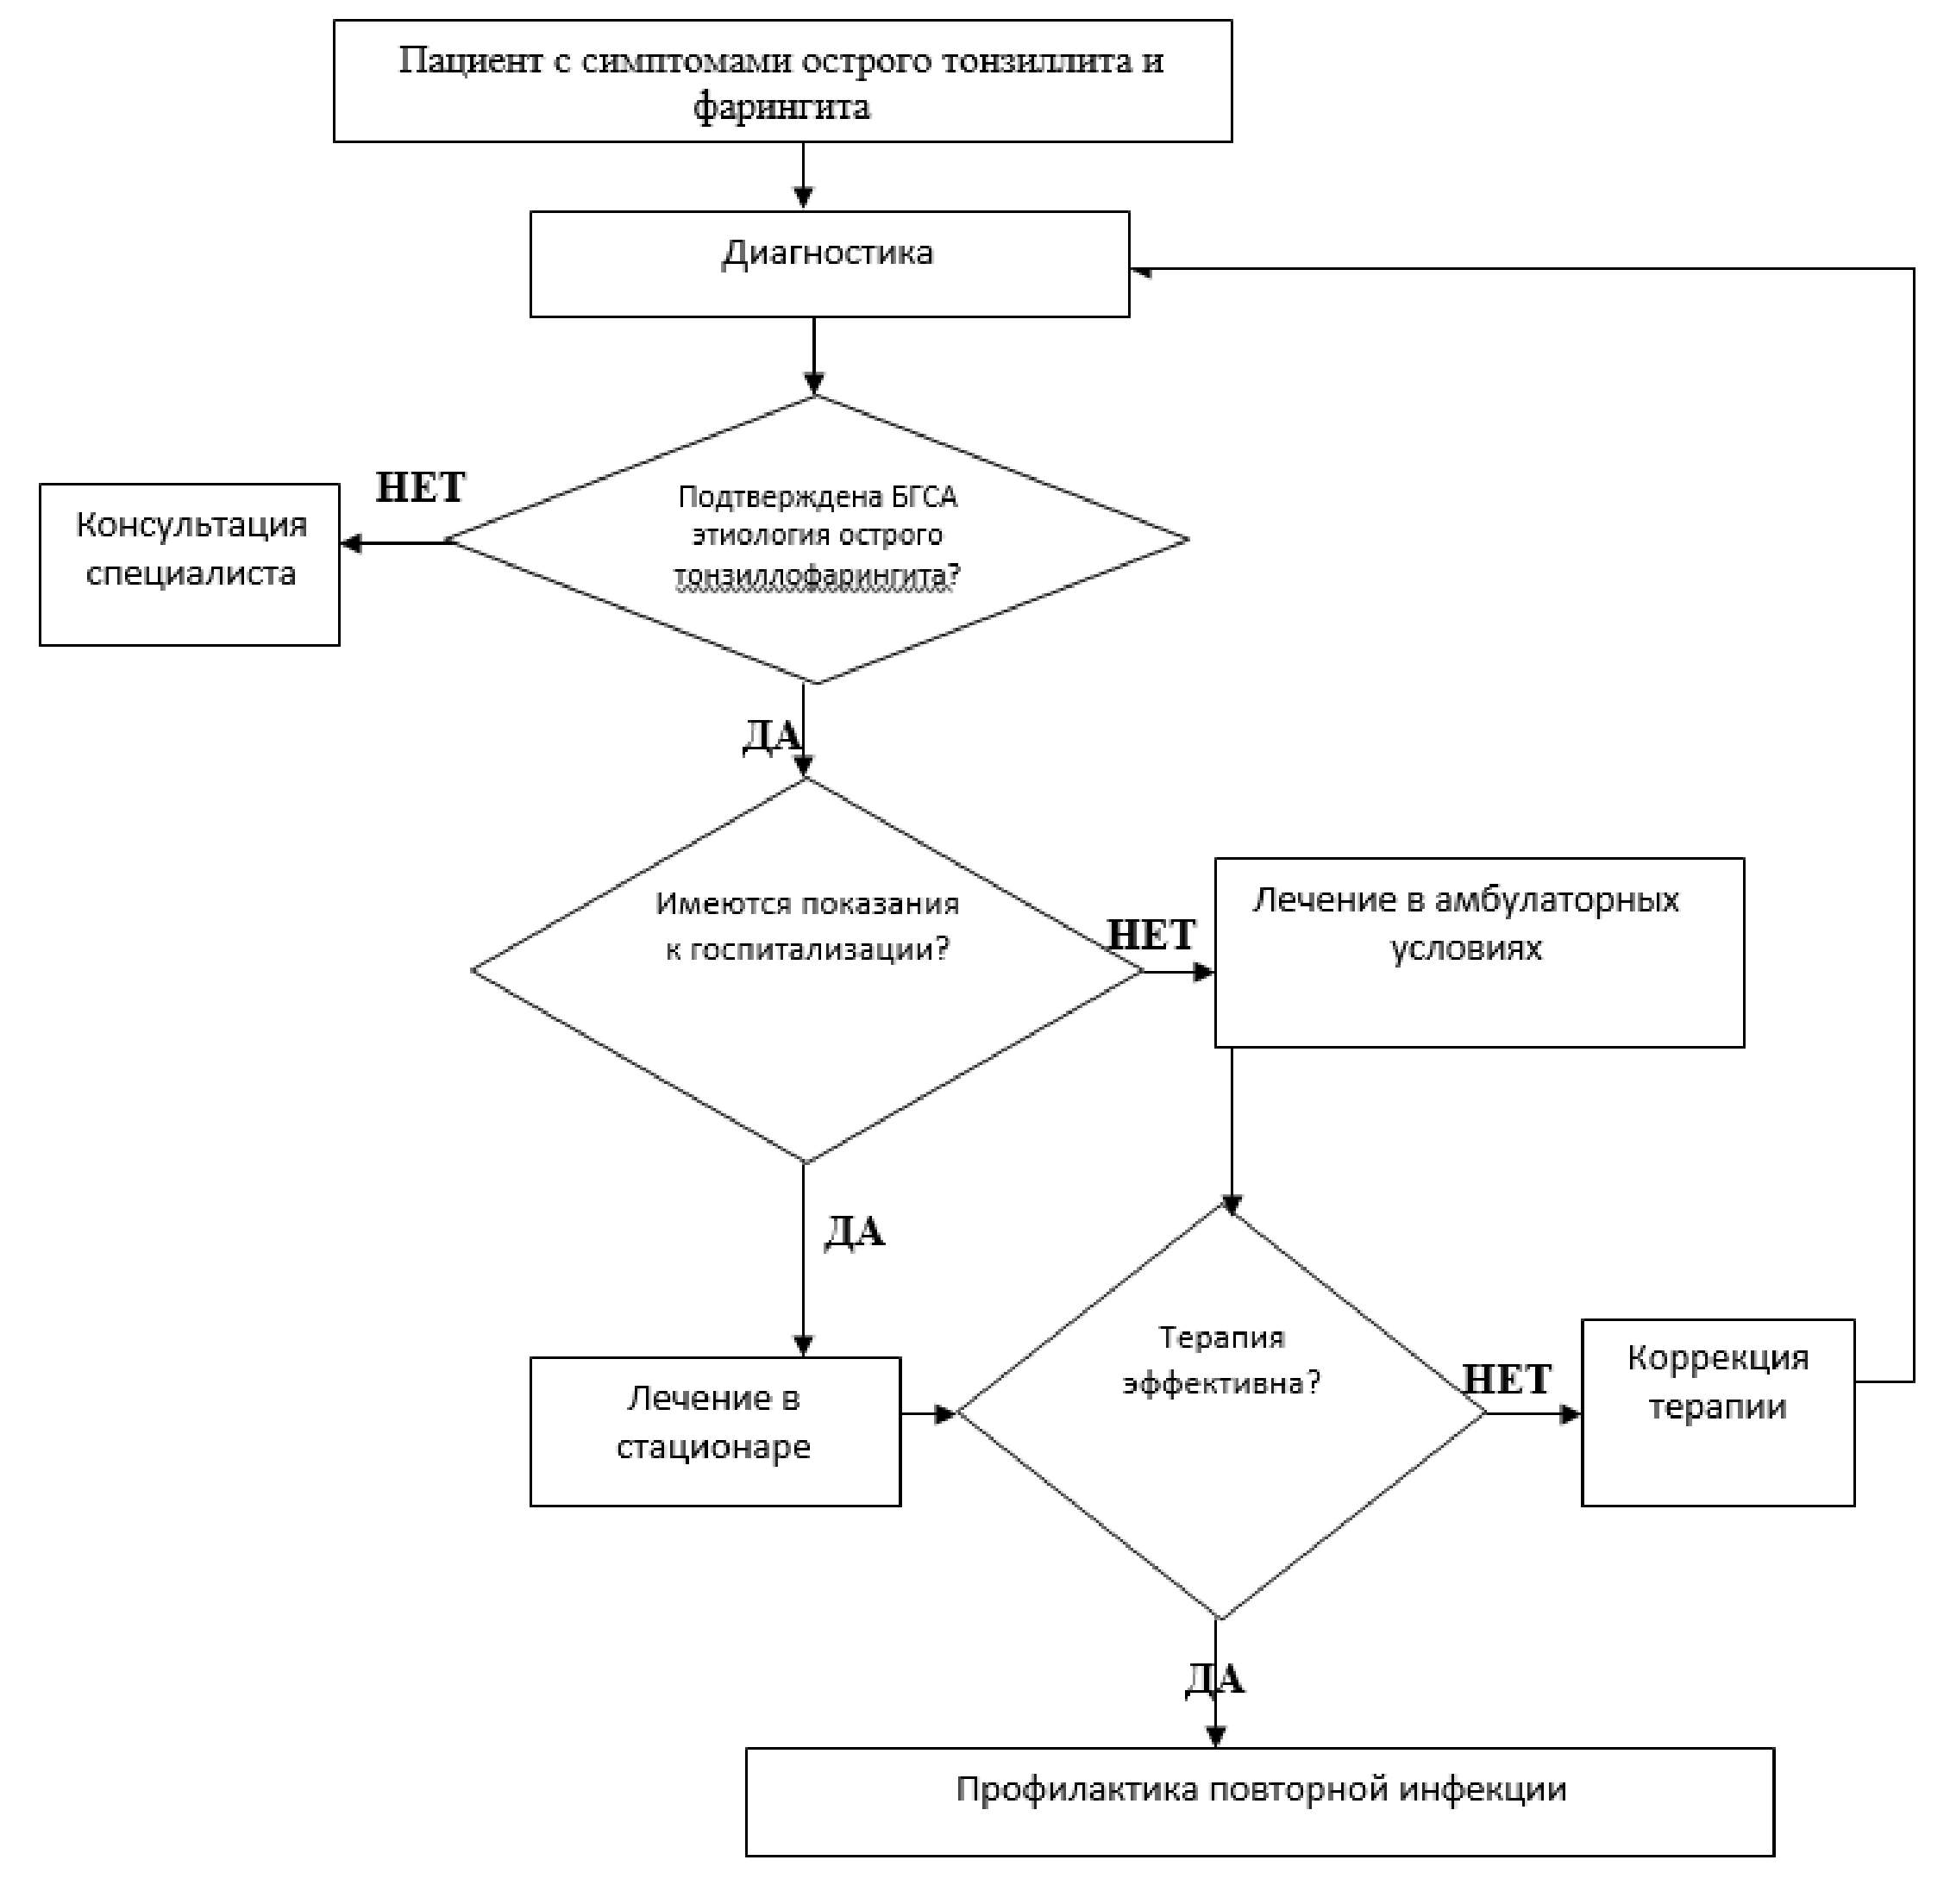

Организация медицинской помощи осуществляется согласно Алгоритму ведения пациента (приложение Б).

Лечение в большинстве случаев осуществляется амбулаторно, врачом-педиатром или врачом общей практики (семейным врачом) или врачом-терапевтом.

Госпитализации в инфекционное отделение, при его отсутствии - в боксированное педиатрическое отделение требуют пациенты в тяжелом состоянии, при необходимости инфузионной терапии ввиду отказа ребенка от еды и жидкости.

Неэффективность лечения, подозрение на гнойное осложнение (паратонзиллярный, парафарингеальный, ретрофарингеальный абсцесс, гнойный лимфаденит), атипичная фарингоскопическая картина (подозрение на новообразование), необходимость хирургического вмешательства (дренирование абсцесса, биопсия, тонзиллэктомия) являются показанием для консультации врача-оторинолариноголога и госпитализации в соответствующее хирургическое отделение.

Выписка из стационара осуществляется при устойчивом купировании проявлений болезни и отсутствии угрозы жизни и здоровью пациента.